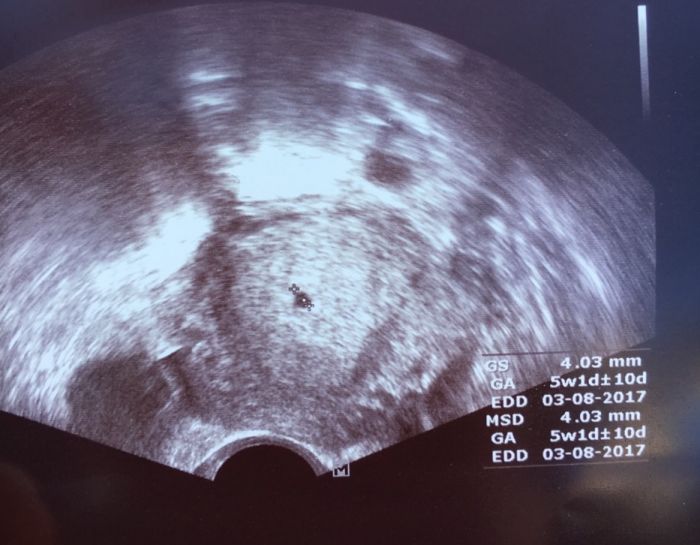

Já včera viděla na Už tohle.. ještě bez srdeční akce.. to je prý brzy. . Byla jsem 5+5.. to podle me ještě dlouho nebude slyset